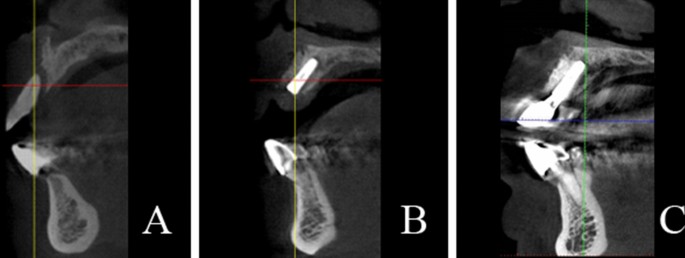

Radiographic examinations were performed at preoperation, immediate postoperative, and 12 months after prosthetic restorations using cone-beam computed tomography (CBCT) (Fig. 2). Thus, we could evaluate the effects of bone augmentation and the progression of bone resorption especially at the implant shoulders and the apical zones of the implants. A measurement of the bone widths was taken around the implants in the plane perpendicular to the long axis of the implants by utilizing a CBCT ProMax 3D Mid unit (Planmeca, Helsinki, Finlandia). We took measurements in the parallel planes which were below the implant neck platform to 0 mm, 1 mm, 2 mm, and 3 mm (Fig. 3). Therefore, the amount of horizontal bone mass could be obtained in each part to evaluate the horizontal bone gain and the resorption of the xenogeneic bone. During the process, 2 physicians repeated the measurement in triplicate and re-measured it 2 weeks later. The average data of the repetitions were taken for statistical analysis.

For horizontal bone gain, the mean bone gain at four planes (0 mm, 1 mm, 2 mm, 3 mm) were 2.40 ± 0.31 mm, 2.81 ± 0.45 mm, 3.35 ± 0.50 mm, 3.76 ± 0.53 mm at immediate postoperative and 1.95 ± 0.19 mm, 2.39 ± 0.38 mm, 2.91 ± 0.56 mm, 3.28 ± 0.63 mm at 12 months after prosthetic restorations. Notably, significant decreases which indicated the mean bone resorption were observed at four planes (p < 0.05). The mean bone resorption at four planes were 0.45 ± 0.28 mm, 0.41 ± 0.36 mm, 0.43 ± 0.31 mm, 0.48 ± 0.31 mm (Table 3), and bone absorption rates were 17.78 ± 9.03%, 13.86 ± 10.55%, 13.02 ± 8.85%, 12.96 ± 8.36% at four levels.